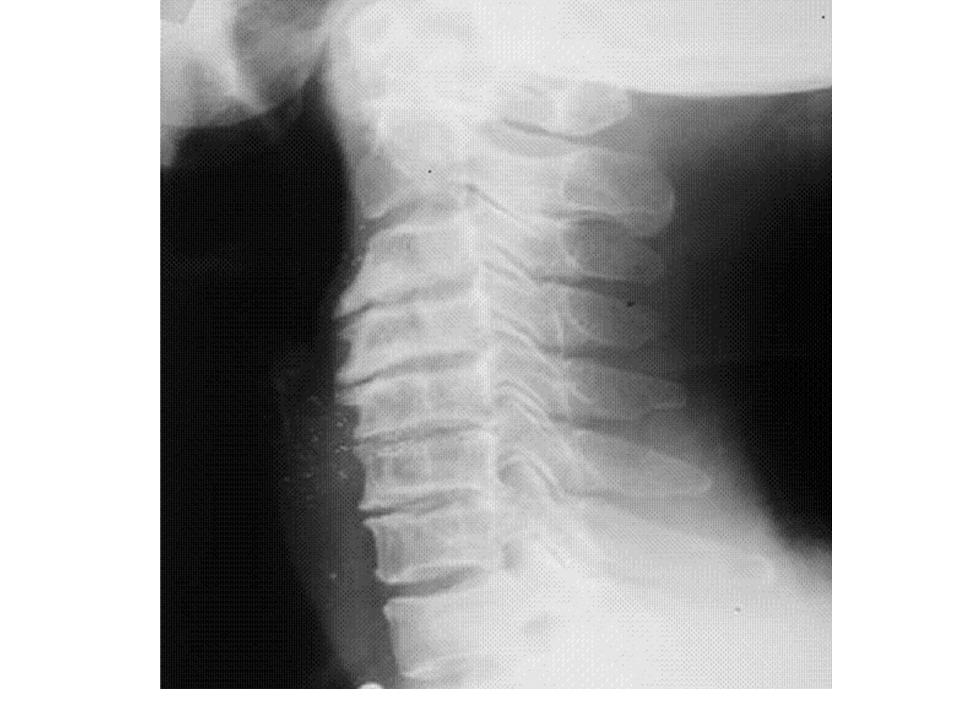

From www.wikidoc.org

Rheumatoid arthritis x ray wikidoc Cervical Arthritis At 30    webmd provides information on cervical osteoarthritis, also known as cervical spondylosis, including causes, symptoms, and treatments. Symptoms include neck pain, stiffness, headache, arm or leg weakness, and referred pain to other parts of the body. The discs may naturally dry out and shrink over time, which can lead to bone spurs and other osteoarthritis signs and symptoms.   neck. Cervical Arthritis At 30.

From www.alamy.com

Xray showing cervical arthritis of the neck Stock Photo Alamy Cervical Arthritis At 30    webmd provides information on cervical osteoarthritis, also known as cervical spondylosis, including causes, symptoms, and treatments.   neck arthritis, also called cervical spondylosis, is a common condition that occurs when the cartilage and bones in the neck gradually wear down over time, leading to joint inflammation, pain,. Symptoms include neck pain, stiffness, headache, arm or leg weakness, and referred. Cervical Arthritis At 30.